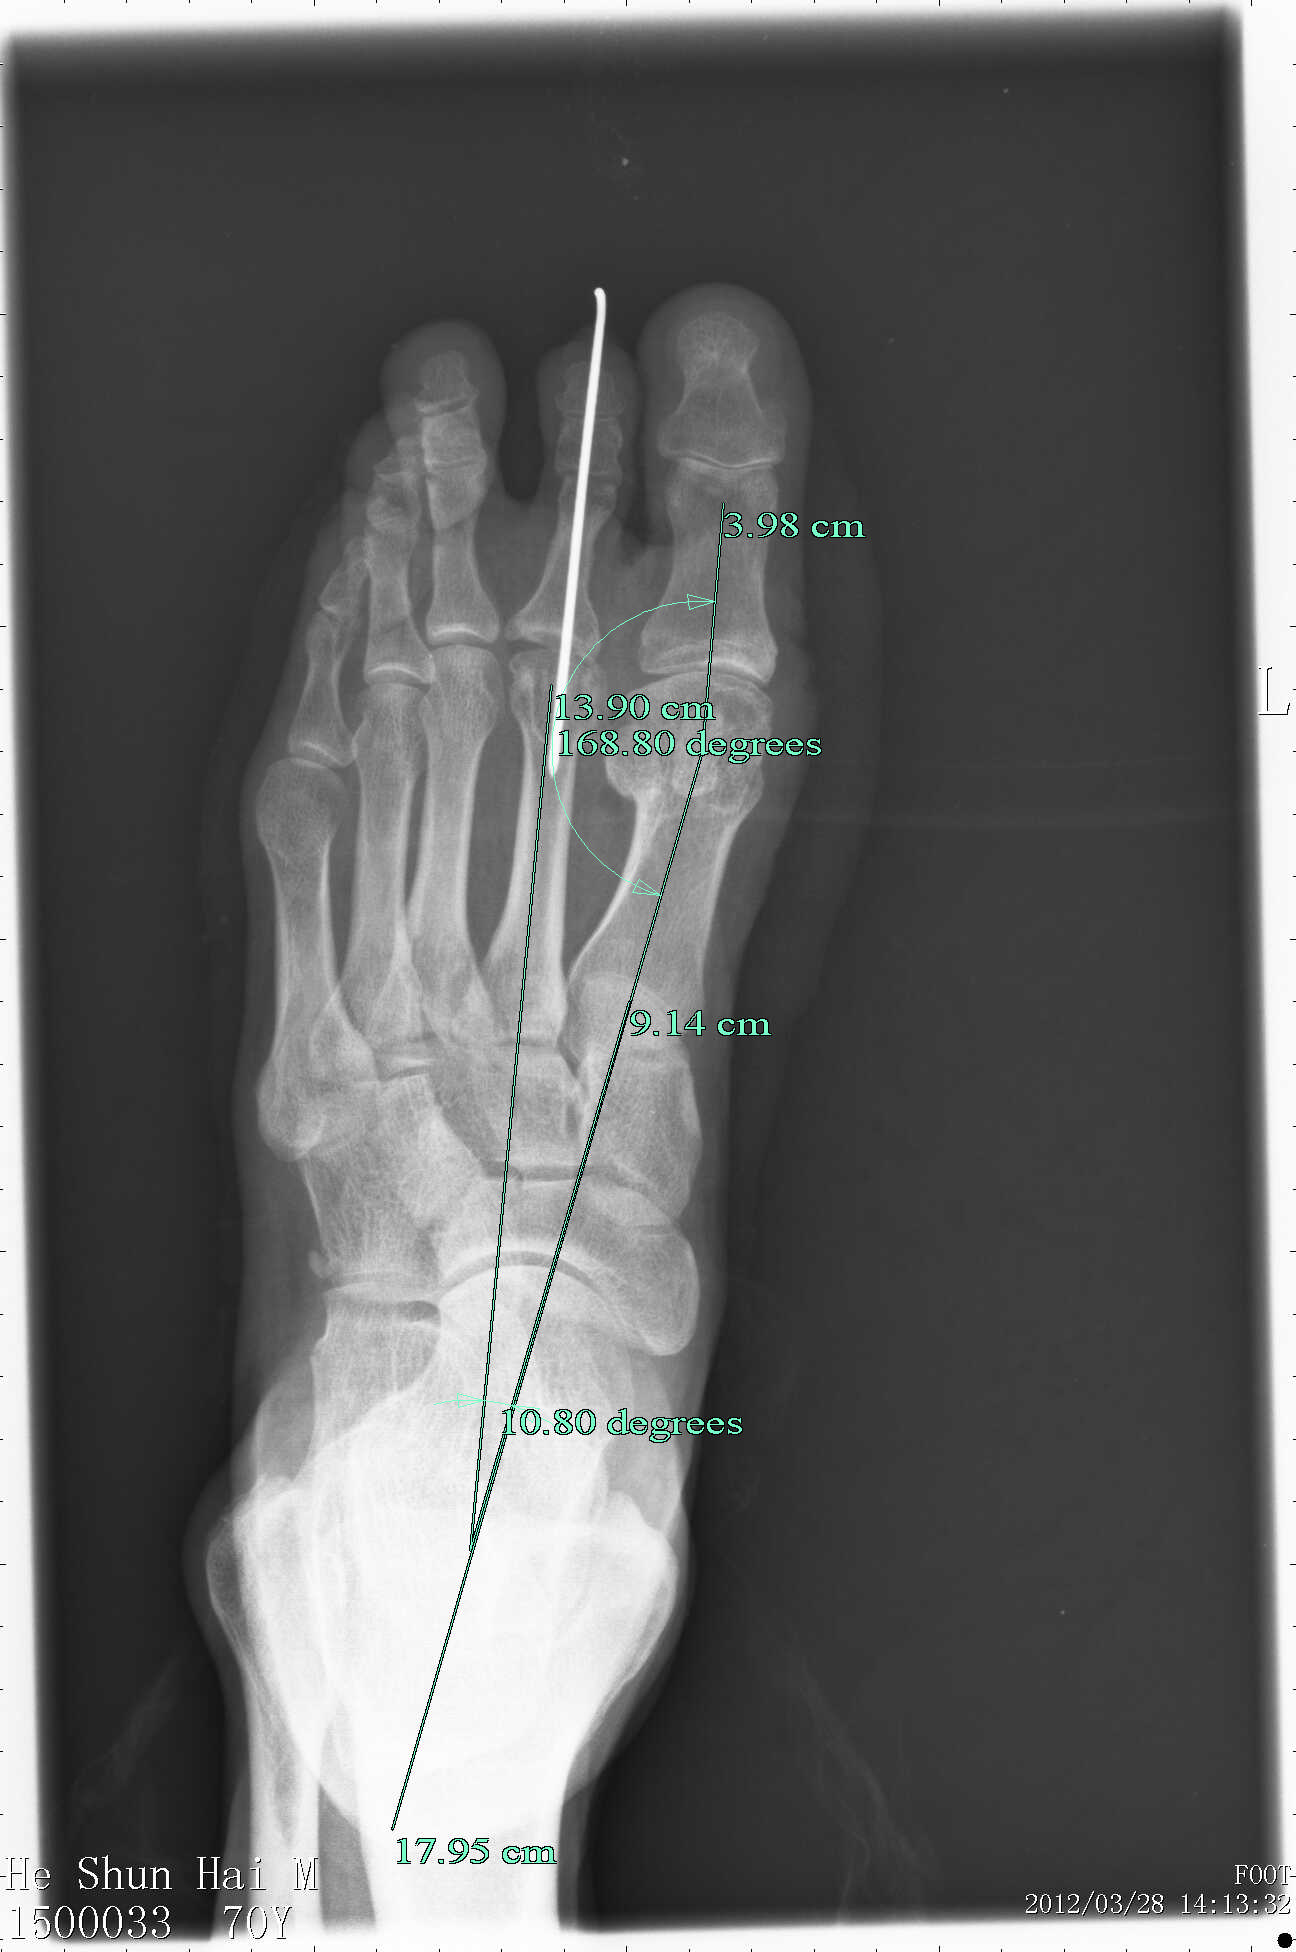

右足第一跖趾关节疼痛十多年

图片尺寸733x889